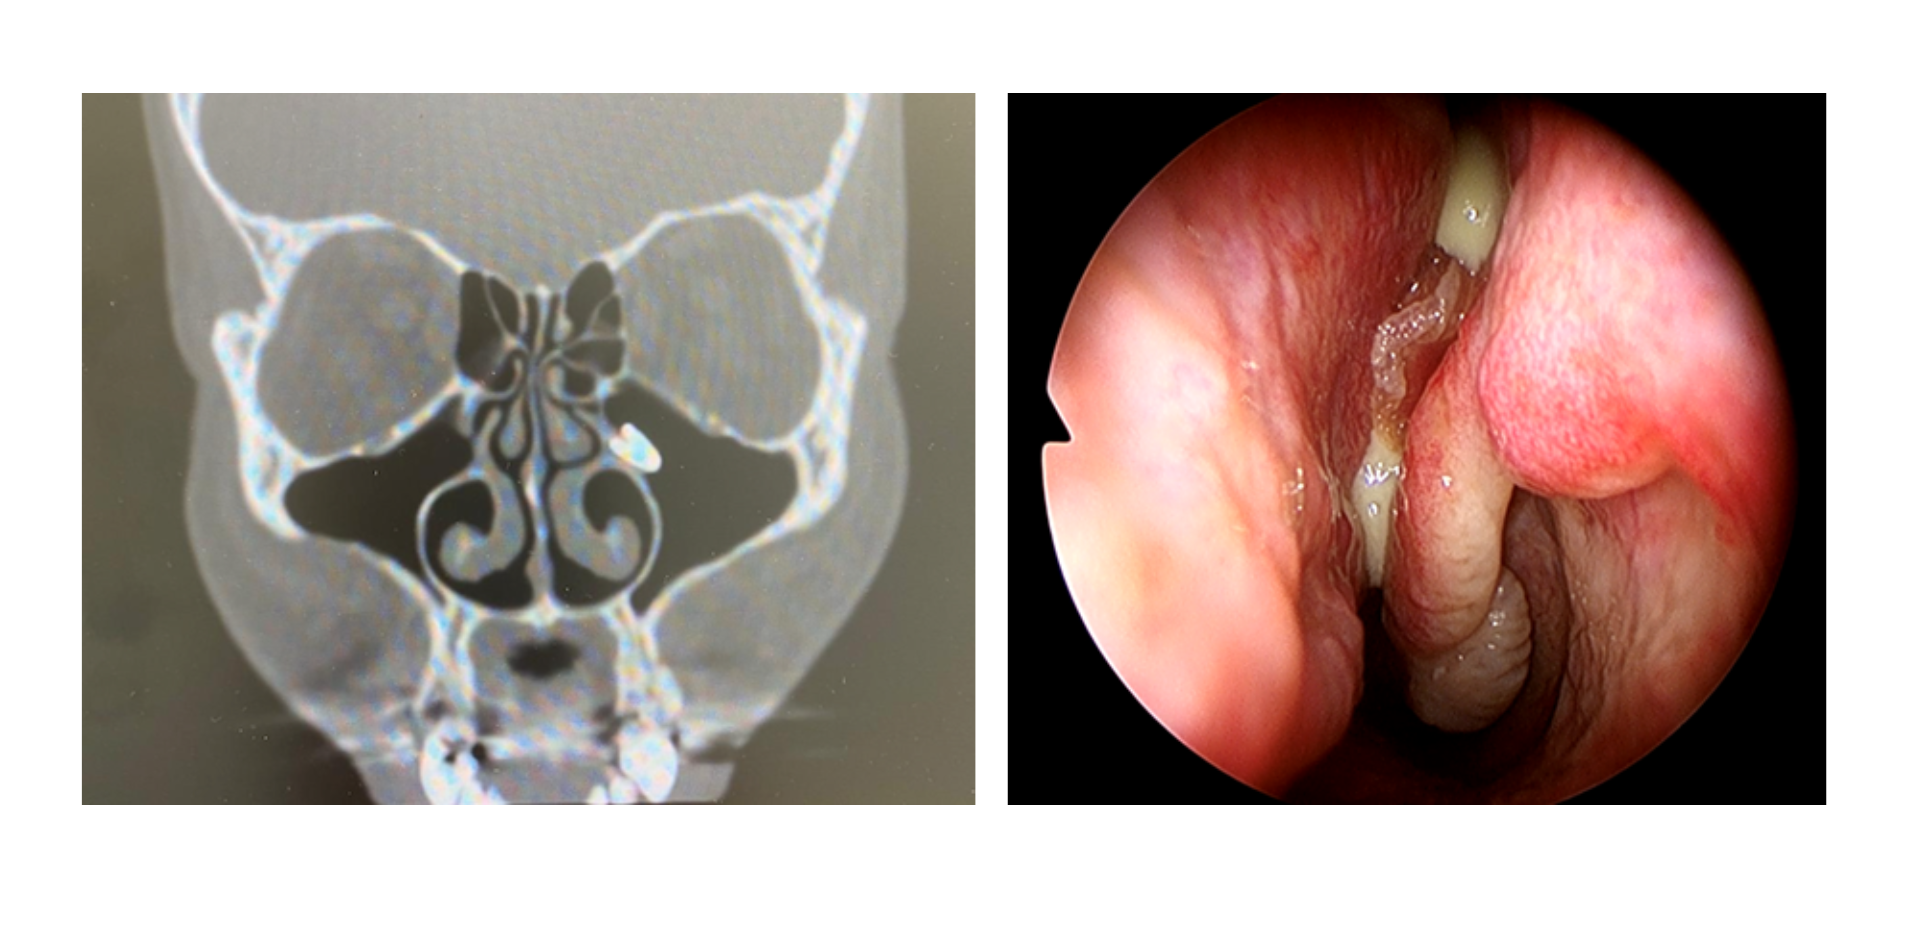

• El seno maxilar detalle. Anatomía topográfica y endoscópica.

• Técnicas de imagen/exploración del seno maxilar

Bloque 2 - Patología/ hallazgos radiológicos relacionados con el seno maxilar

• Quistes y mucoceles sinusales. Quistes del seno maxilar

• Sinusitis:

- Generalidades sobre la sinusitis

- Etiología de la sinusitis maxilar

- Diferencias entre sinusitis rinógenea y odontógena